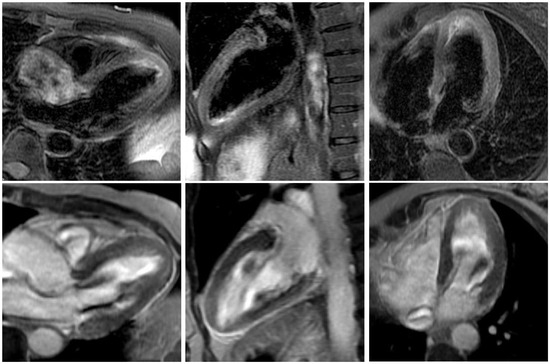

Figure 4. Cardiac magnetic resonance imaging long-axis still frames with T2 STIR (short T1 inversion recovery) imaging (top row) and late enhancement (lower row). Apical hyperenhancement in the T2 imaging without late enhancement of the apex, indicating oedema without infarction or scarring. This finding is typical of takotsubo cardiomyopathy. (Three-chamber view, two-chamber view, four-chamber view from left to right.).